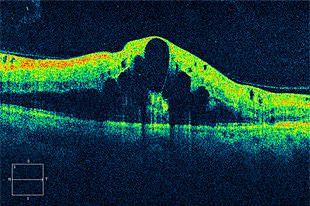

黄斑前膜

網膜の中心である黄斑上に膜が張り、視力低下や、歪みをきたします。

術前

術後